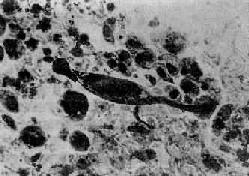

图9-26 石棉肺

图中央可见典型石棉小体,两端肥大,呈分节状,周围为尘细胞